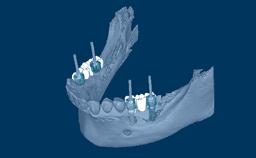

在制取种植体印模时,使用精确制作的取模柱来记录种植体的位置、排列和角度方向。无论是遵循传统(即替代体)还是数字化印模制取流程,印模都会记录这些与周围硬组织和软组织相关的信息。本模块将介绍传统印模技术和所涉及的所有参数。

- 概述传统种植体印模的工作流程